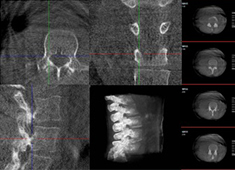

三維重建技術在醫學影像診斷中的應用價值

三維重建技術在醫學影像診斷中的應用非常廣泛,主要包括以下幾個方面:1.診斷疾病:通過三維重建技術,醫生可以更直觀、清晰地觀察到患者體內的異常情況,如腫瘤、骨折等,從而更準確地診斷疾病。...